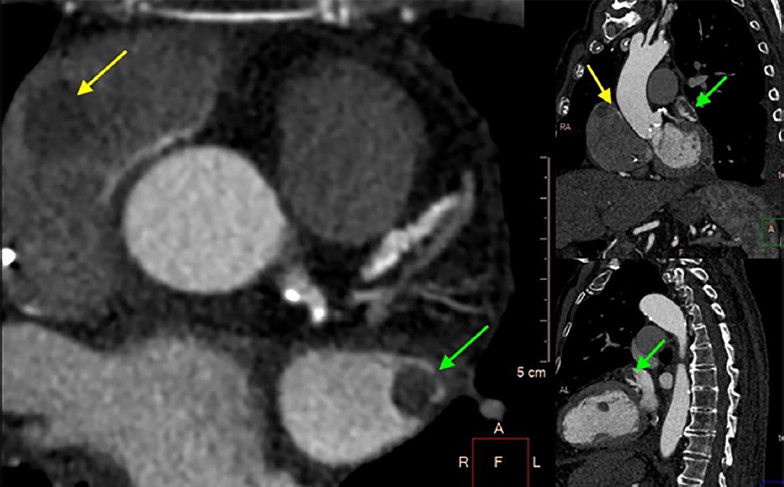

En el estudio se observan defectos de relleno de contraste en fases precoces y tardías en el techo de la aurícula derecha próximo a la orejuela y en orejuela auricular izquierda, compatibles con trombos (Figuras 1 y 2).

La tomografía cardiovascular es un excelente instrumento para evaluar trombosis auricular, que se observa como una estructura definida con bordes netos, que genera defectos de relleno del contraste tanto en fases precoces como tardías luego de la infusión del mismo (para distinguirlo de los fenómenos de rémora, que pueden tener defectos precoces que corrigen en fases tardías). Tiene una elevada sensibilidad y especificidad para detección de trombos en aurícula izquierda. 3 Sin embargo, no siempre es sencillo lograr un adecuado contraste de las cavidades derechas y particularmente la orejuela derecha, en especial en estudios dirigidos a evaluar “estructuras izquierdas” (coronarias, venas pulmonares, válvulas), por lo que una trombosis auricular derecha puede pasar desapercibida. La baja señal en unidades Hounsfield en la tomografía no contrastada o el ratio de las unidades Hounsfield entre trombo y la aorta utilizando equipos de doble fuente 4 pueden ayudar a la identificación de la trombosis auricular mediante tomografía cardiovascular.